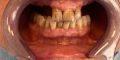

- Prima

La chirurgia computer guidata permette di eseguire interventi di implantologia in modo rapido e minimamente invasivo: un programma apposito elabora gli esami radiologici in 3D con la Tac individuando i punti precisi dell’osso dove vanno inseriti i nuovi denti. Successivamente si realizza la maschera chirurgica che il paziente indossa durante l’intervento; la maschera presenta dei fori che replicano le posizioni esatte degli impianti. Con questa procedura, a differenza dell’implantologia tradizionale, non vi è bisogno di tagliare e staccare la gengiva né di esporre e ricostruire l’osso. Non solo: i tempi di recupero sono molto più rapidi perché il gonfiore e il dolore post operatorio sono estremamente ridotti, così come il sanguinamento che è notevolmente contenuto.